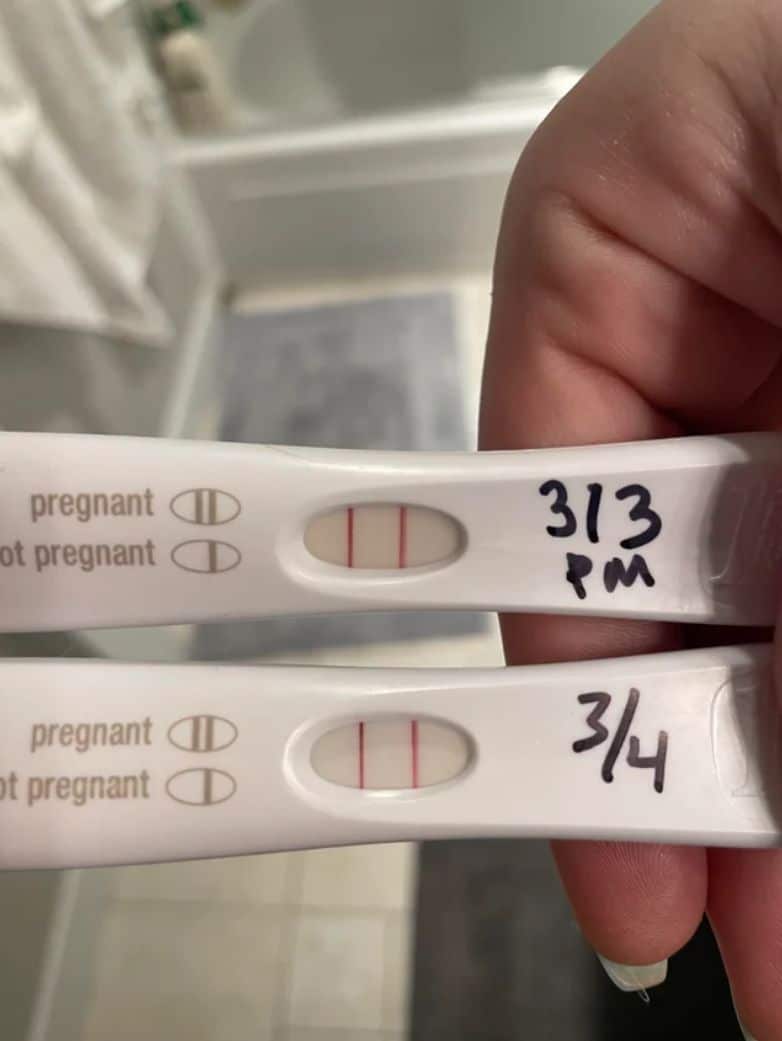

To solve the mystery, this woman had the children take a DNA test.

But Allen’s case was even rarer than that might suggest as this happened as a result of an incredibly uncommon phenomenon known as superfetation.

This is a term given for when a woman is pregnant with two babies who aren’t twins at the same time and according to their chief medical contributor — Dr. Jennifer Ashton — there still isn’t a solid hormonal or physiological explanation for why it happens.

A reproductive medicine specialist named Karen Boyle also said that there were only 10 previously reported cases of superfetation ever occurring.